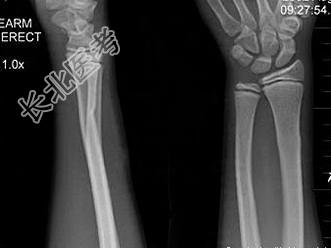

- 单项选择题男,10岁, 有外伤,根据所提供图像, 选择最佳选项 ( )

A、未见异常

B、骺移骨折

C、青枝骨折

D、腕关节脱位

E、踝关节脱位